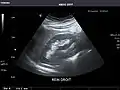

- Right kidney

Kidneys: Right and left kidneys measure 11.5 cm and 12 cm in length respectively. No hydronephrosis. Small left lower pole kidney cyst.